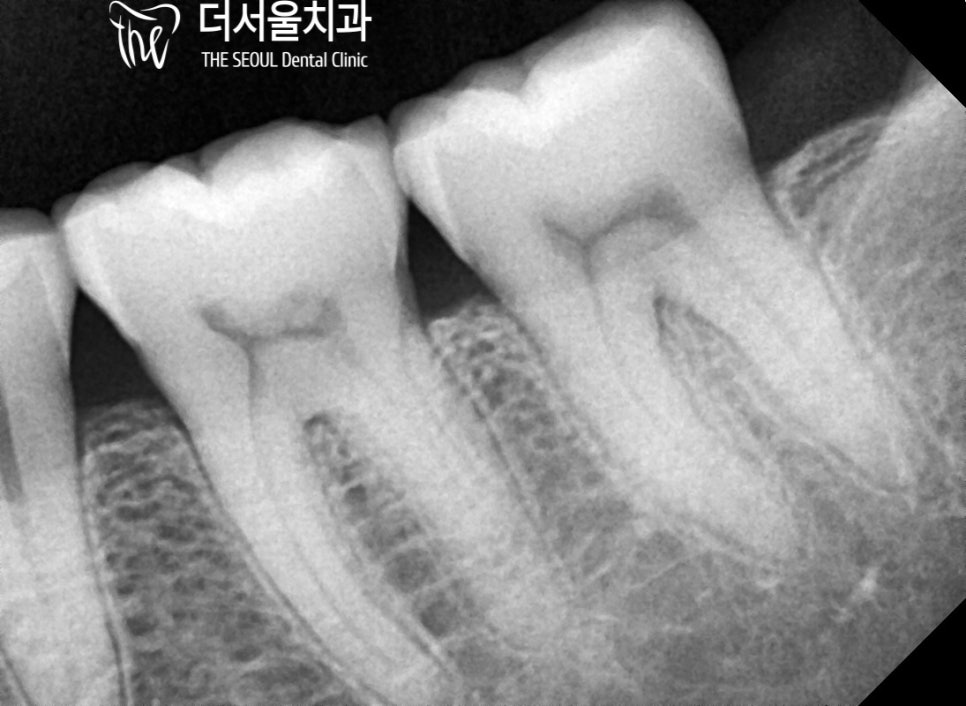

다행히 예상했던 그대로

금간치아 가 발견되었긴 했지만

균열의 범위가 그리 크진 않았습니다.

환자의 경우 치관 부위의 파절이였으며

약간의 신경 손상도 나타나 있었기 때문에

신경치료를 동반한 크라운 수복으로

문제를 개선하기로 방향을 잡았습니다.

계획했던대로 감염된 치수 조직을 제거한 뒤,

충전재를 사용하여 뿌리 끝(apex)까지

빈 공간이 없도록 채워넣었습니다.

뿌리 끝까지 확실하게

채워진 것을 확인할 수 있는데요.